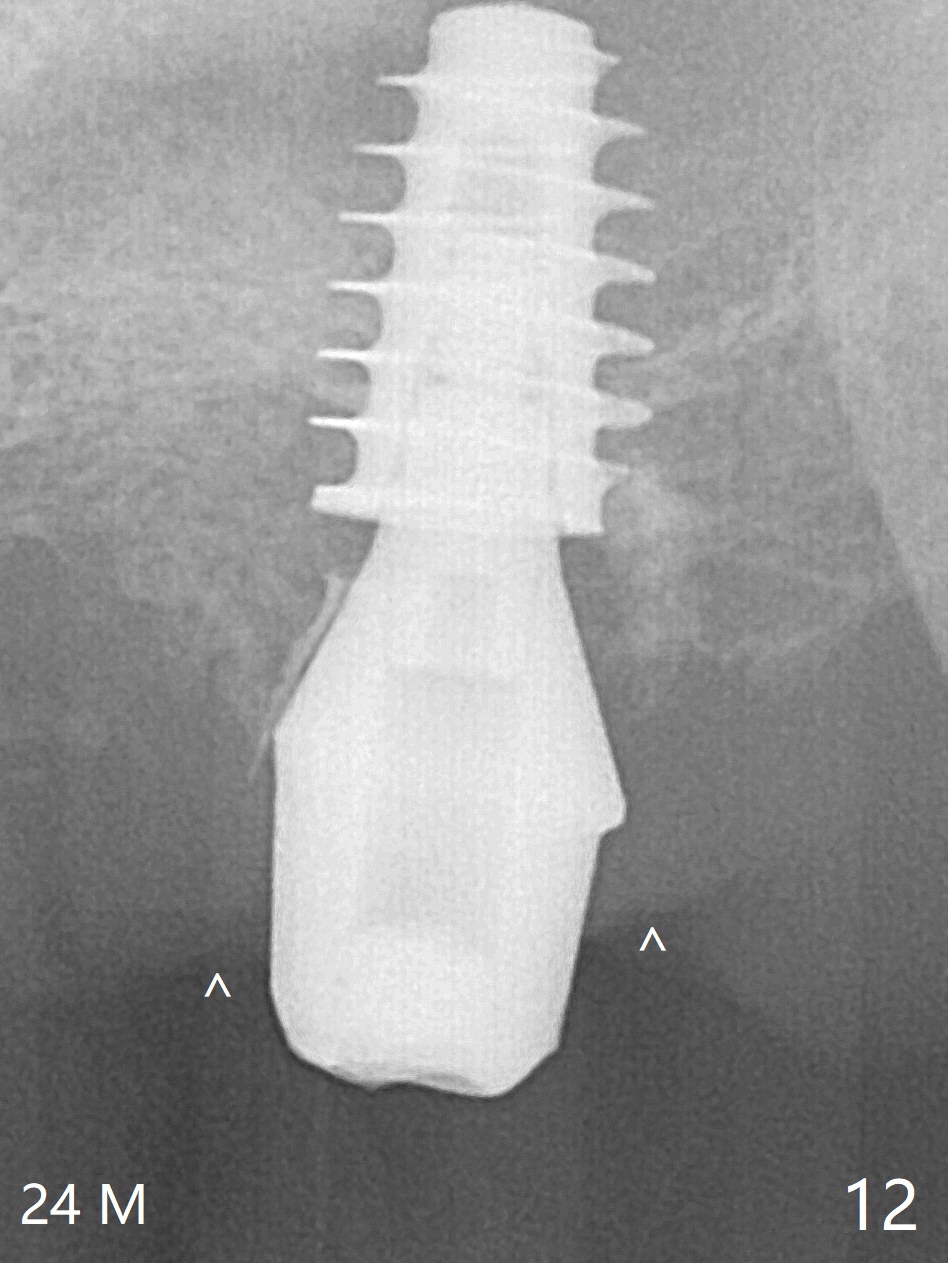

One month later, bone graft is placed mesiopalatal to the implant at #15 (Fig.7 *,8) while a 3.8x13 mm implant is placed at #13 following bone expansion (using Magic Split and Magic Expander 3.0 mm (abutment 5.5x4(5) mm). Another month later, the tooth #16 is extracted to create space for #15 restoration. Two weeks later the abutment at #15 is found to be unstable (2.5 months postop). Local oral hygiene is poor. The abutment is removed and a 6x4 mm healing abutment is placed with mild tenderness. It appears that the limited bone height is associated with low stability with CMC. Three months later (5.5 months postop), the implant seems to be stable (Fig.9,10). The implant remains stable clinically 7 months postop (Fig.11). The bone graft appears to mature and covers the abutment with provisional 24 months postop, the bony changes is related to the thick gingiva (Fig.12 ^).